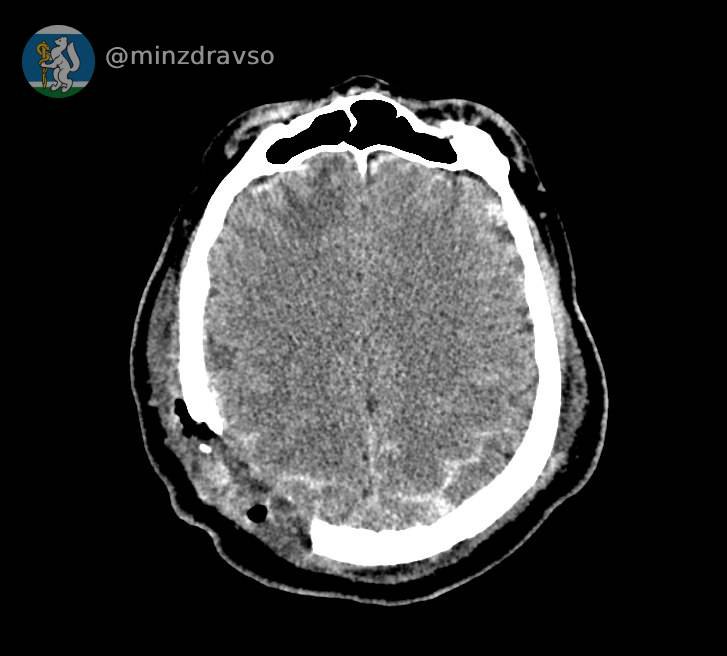

В Серове 57-летнего мужчину ударила стрела строительного крана, расколов ему череп. В критическом состоянии мужчина поступил в единственное на севере нашего региона стационарное отделение скорой медицинской помощи, действующее на базе Серовской городской больницы. Высокоточный компьютерный томограф помог быстро диагностировать травмы и выявить расположение повредивших мозг костных отломков, самый острый из которых мог в любую минуту стать причиной гибели пациента. Слаженное взаимодействие серовских реаниматологов позволило стабилизировать состояние пострадавшего.

Профильные специалисты из Екатеринбурга в ходе телеконсультации подтвердили необходимость перегоспитализации уральца в ближайший межмуниципальный медицинский центр. Мужчину экстренно доставили в Городскую больницу №1 Нижнего Тагила, где его ожидала операционная бригада. Нейрохирург Дмитрий Неволин, анестезиолог-реаниматолог Аслам Абдуев и операционная медсестра Нина Дмитриева удалили отломки костей, гематомы, восстановили целостность твёрдой мозговой оболочки.